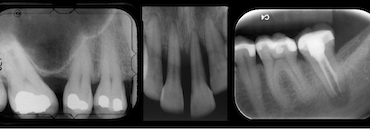

Dental x-rays help your dentist see underlying issue not obvious to the naked eye. The arrows show dental decay and the areas most commonly affected by dental decay. Do you really need dental X-rays? Yes, absolutely. Dental X-rays are a screening procedure that allows the dentist to get “the full picture” and to understand what […]